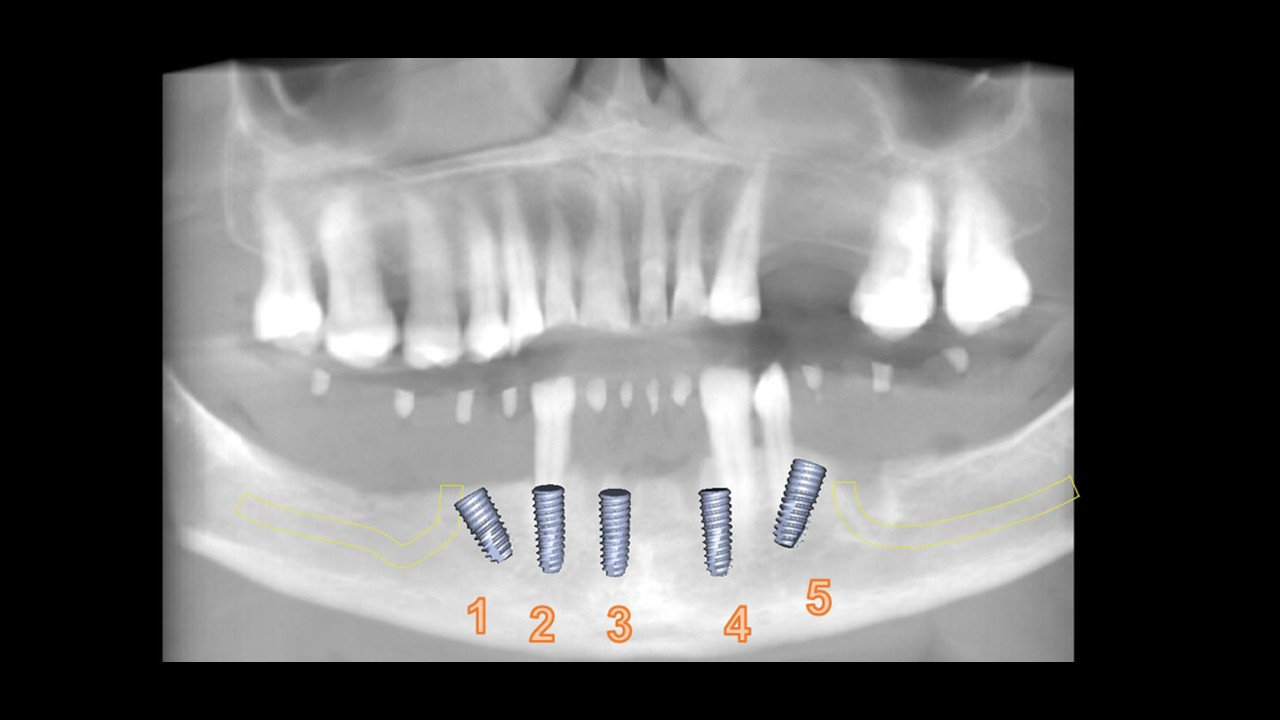

• Instalación de guía CX para posicionamiento de IOI (posiciones 4.5, 4.3, 4.1, 3.3, 3.5).

• Implantes dentales Osstem TSIII Superficie SOI Ø4.0x8.5mm (#1), Ø4.0x10mm (#5), Ø3.5x10mm (#2, #3, #4).